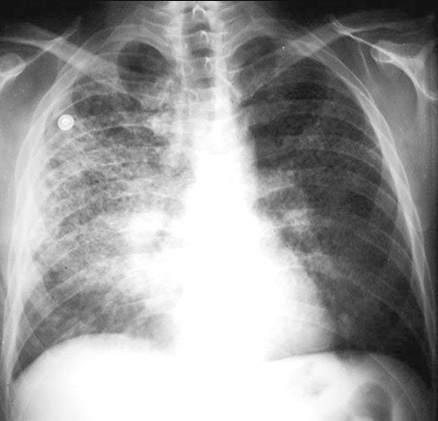

End Stage Interstitial Fibrosis

Note "honeycombing" evident in right middle and upper lung field.

In end stage interstitial fibrosis, there is dilatation of bronchioles which presents as cystic spaces.